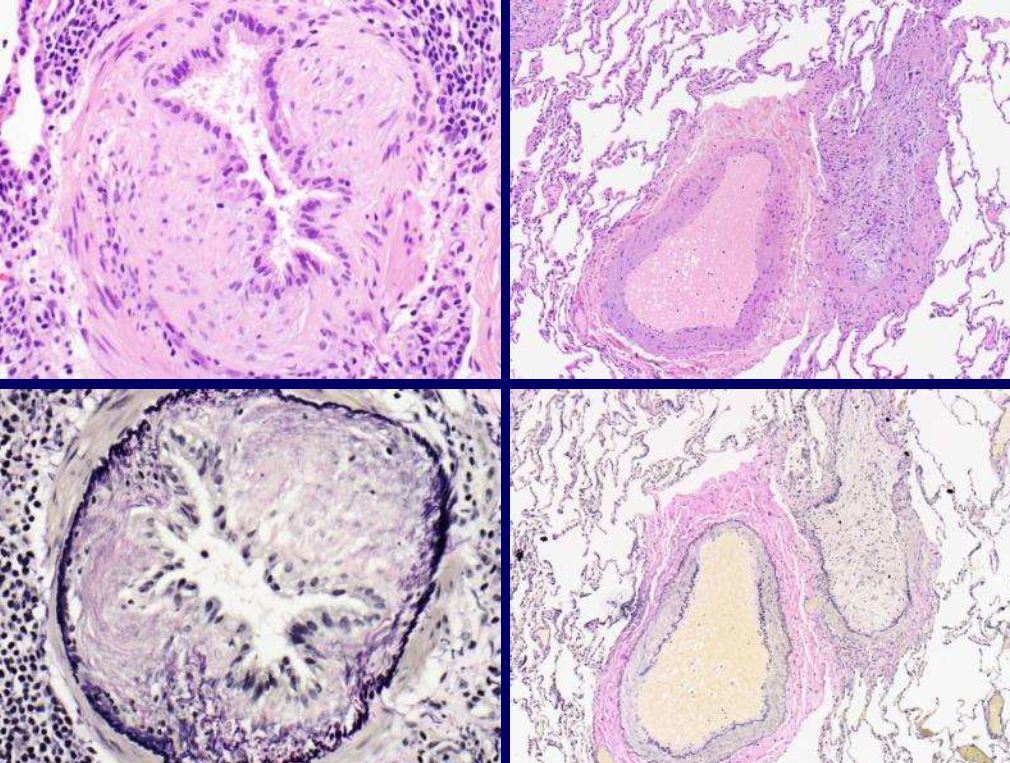

What lesion is this?

Plexiform lesion associated with pulmonary hypertension

The entity shown is a rare cause of pulmonary hypertension and is characterized by abnormal capillary proliferations that grow along alveolar walls and into structures such as airways and venules which may compress venules causing increased pulmonary vascular pressure. What drug must you NOT USE to treat?

Pulmonary capillary hemagiomatosis (PCH) DO NOT use endothelin antagonists! Disease importance made clear due to treating ppl with pulm hypertension with endothelin antagonists. PCH patients develop life threatening complications if treated with this.